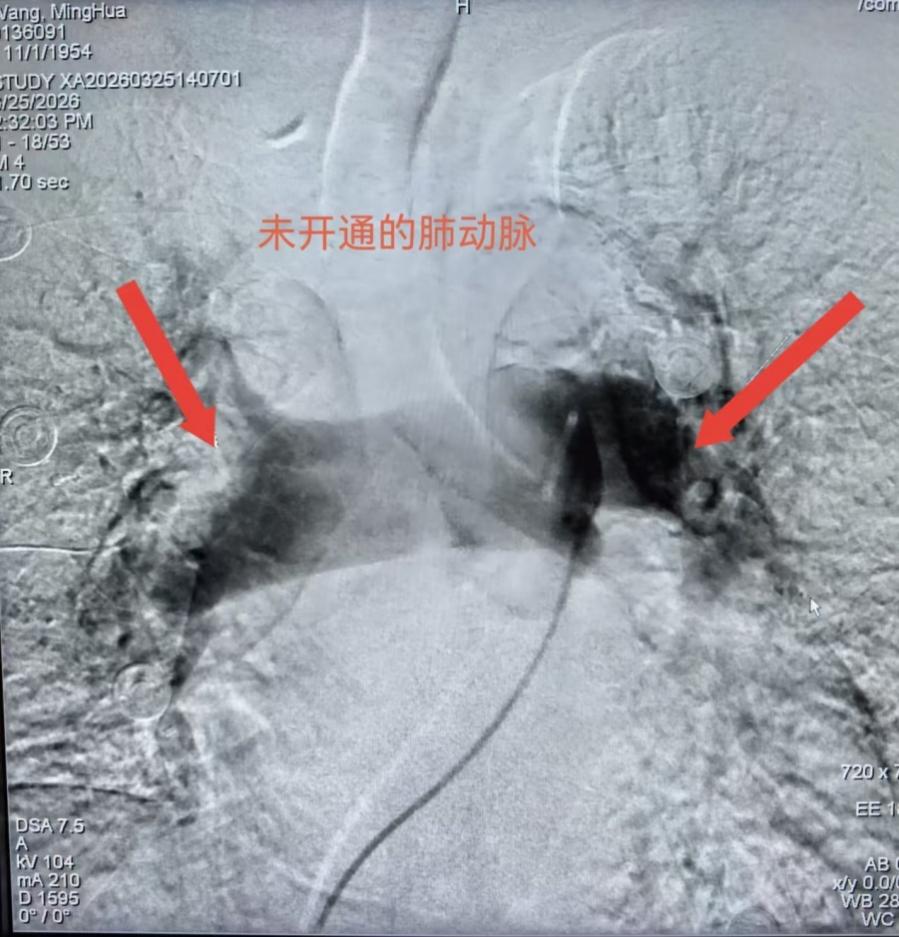

患者为71岁男性,因头晕、胸闷十余天入院治疗。入院后完善相关检查,提示D-二聚体升高,血气分析显示低氧血症、低碳酸血症,经CTPA检查后确诊为双肺肺栓塞。肺栓塞发病急、病情凶险,随时可能危及生命,玉林市红十字会医院心血管内科二区介入团队第一时间评估患者病情,快速制定个性化手术方案。

手术在介入导管室进行,医护团队配合有条不紊。医生进行右股静脉穿刺、置入鞘管及造影导管操作时,护理人员精准完成给药、器械传递等配合工作,保障手术流程顺畅推进。术中造影清晰显示,患者右肺主干、右上肺及左肺动脉存在多发血栓,且手术中患者突发心率骤降至30次/分,病情再度告急。